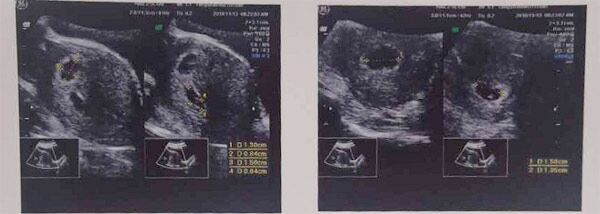

(张女士B超检查报告)